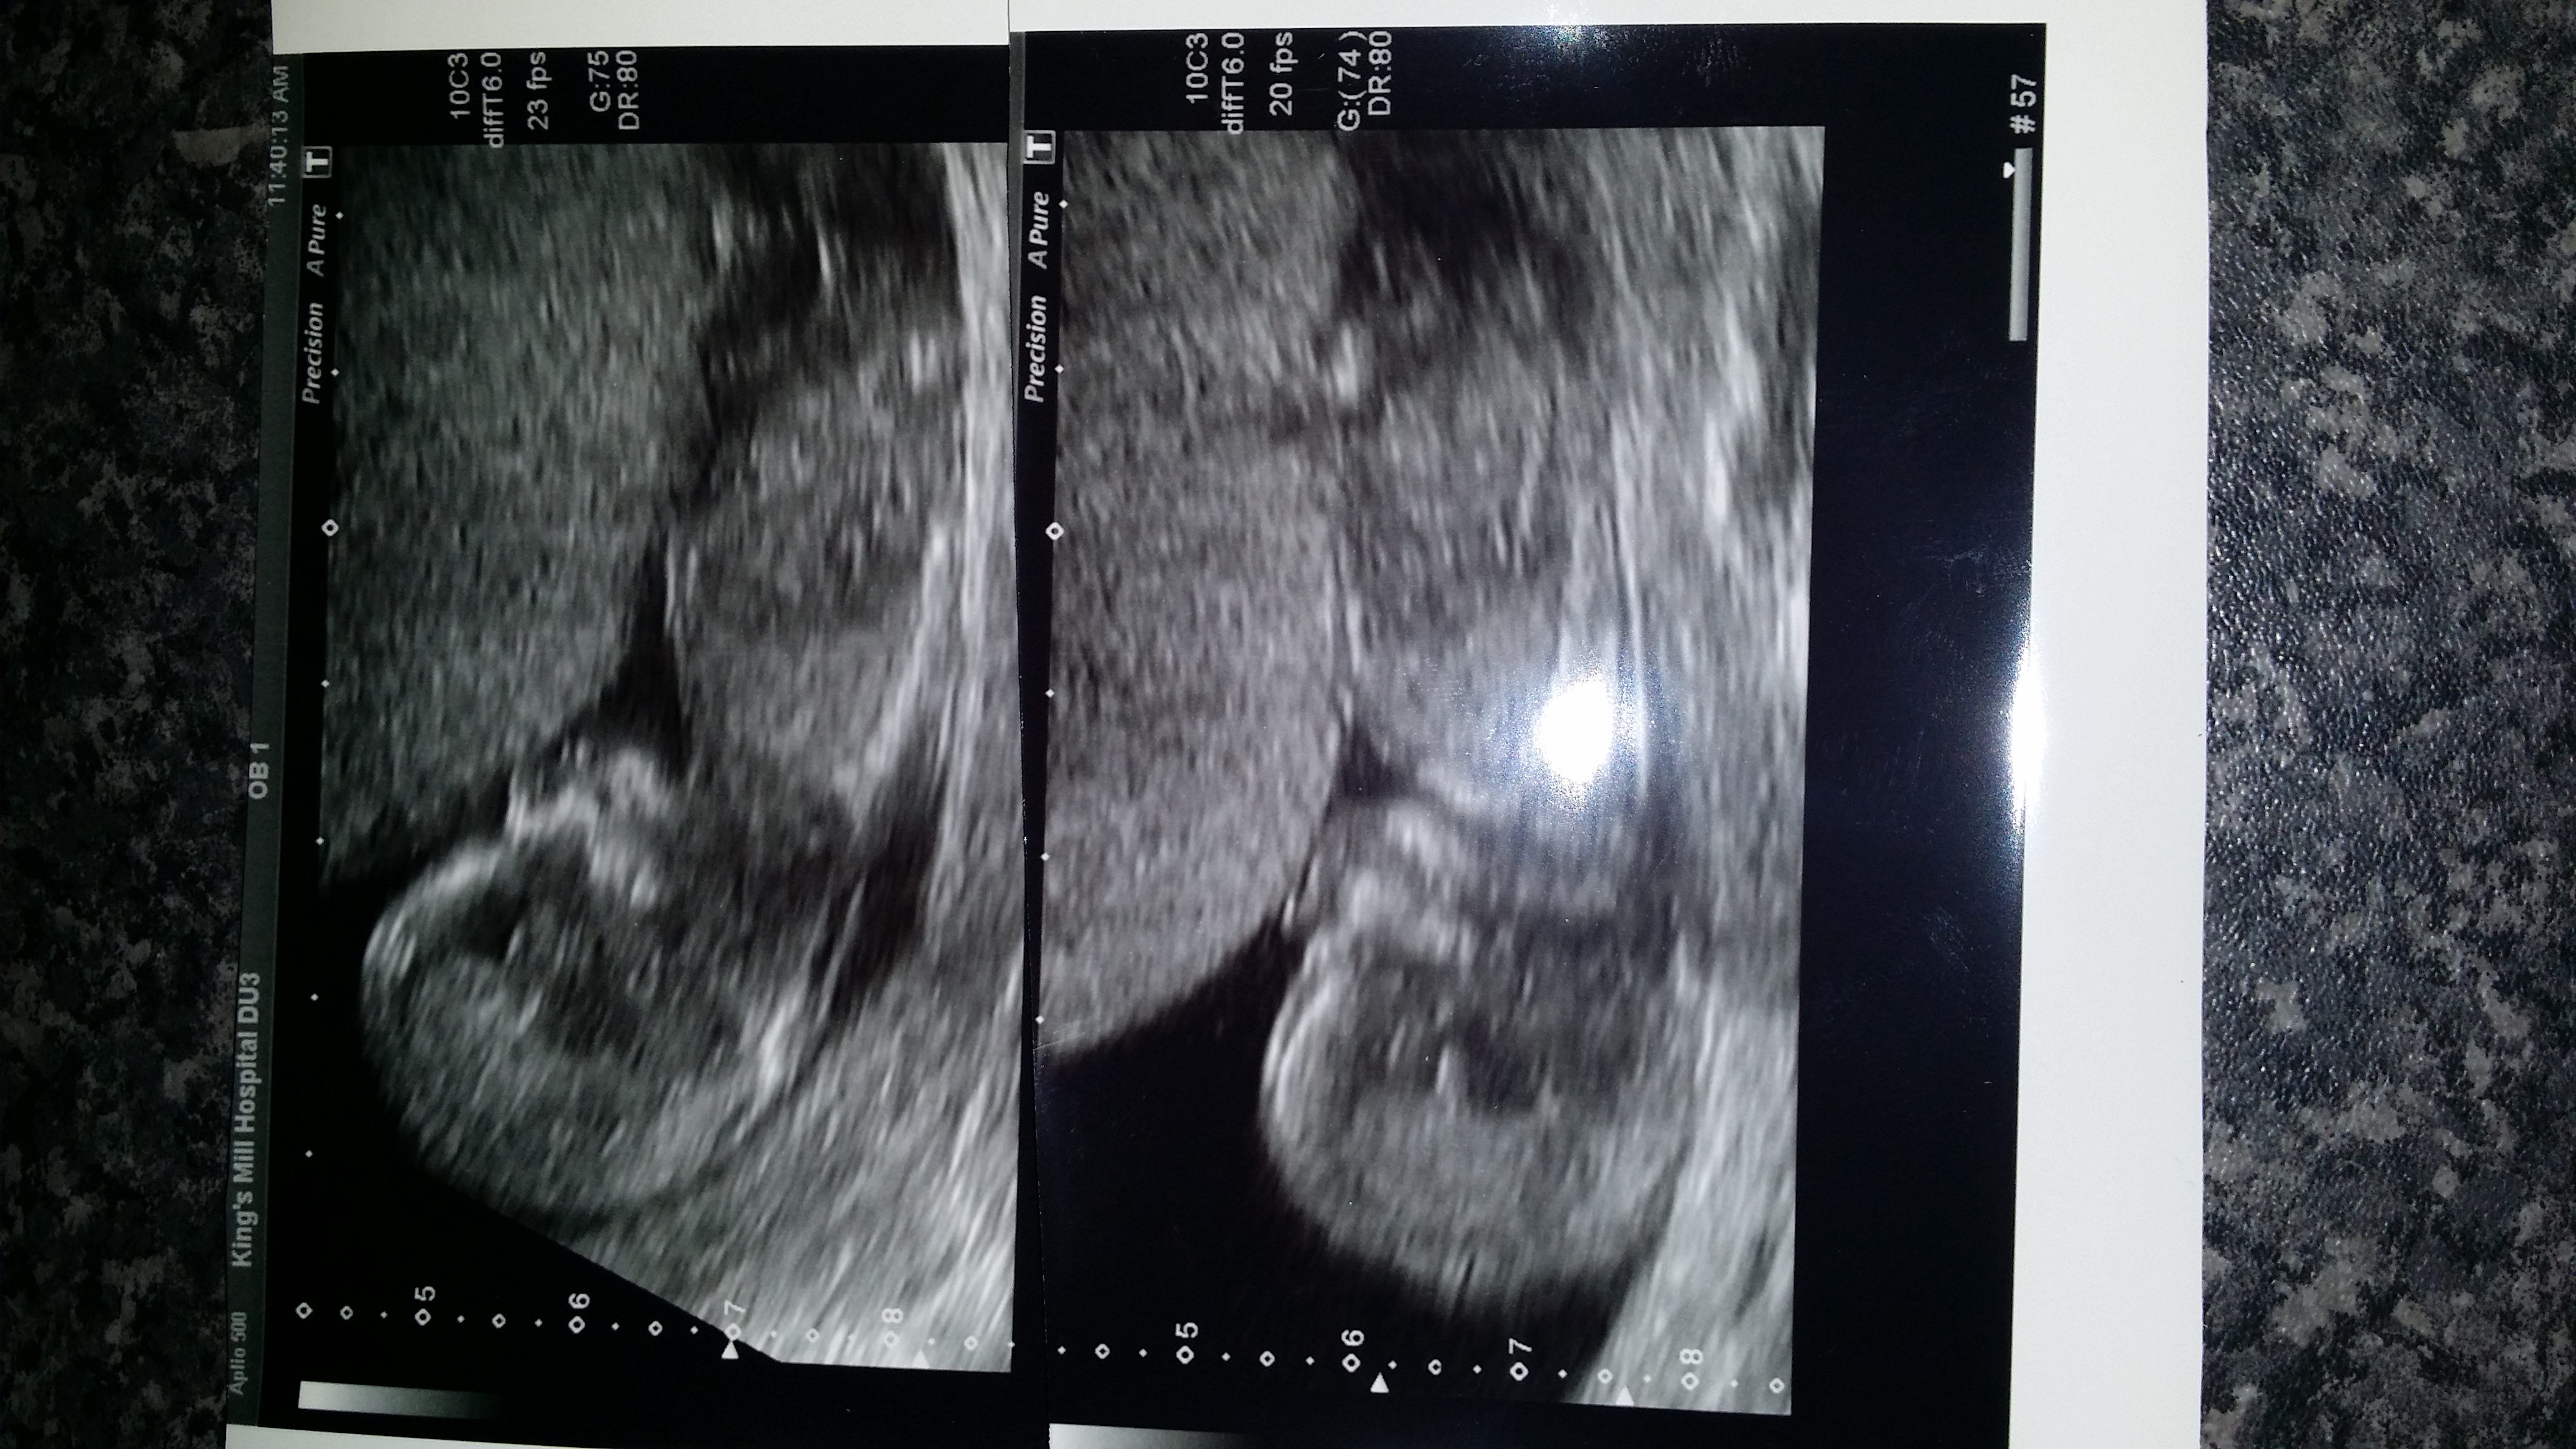

Hey folks. I'm new here. Hoping to get some guesses on my 12w 5days scan picture of our baby due 8th Jan. We have 2 boys already 💙💙So hearing girl 💜would complete us. Super excited about finding out sex on the 23rd July. Does anyone care to take a guess? & be honest :) Thank u xxxAttachment 19685